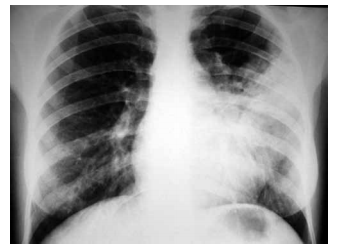

Mulher, 68 anos, sem antecedentes mórbidos, apresenta dor torácica ventilatório-dependente, de forte intensidade com piora à inspiração profunda e dispneia intensa. Recebeu alta há 15 dias após internação para cirurgia de correção de fratura de colo de fêmur. Exame físico: bom estado geral, taquipneica leve, afebril, PA = 120x70 mmHg, saturação periférica de oxigênio = 89% em ar ambiente, ausculta cardíaca normal e ausculta pulmonar com estertores crepitantes finos em bases. Realizados eletrocardiograma e tomografia computadorizada de tórax com contraste, ilustrados a seguir.

Mulher, 68 anos, sem antecedentes mórbidos, apresenta dor torácica ventilatório-dependente, de forte intensidade com piora à inspiração profunda e dispneia intensa. Recebeu alta há 15 dias após internação para cirurgia de correção de fratura de colo de fêmur. Exame físico: bom estado geral, taquipneica leve, afebril, PA = 120x70 mmHg, saturação periférica de oxigênio = 89% em ar ambiente, ausculta cardíaca normal e ausculta pulmonar com estertores crepitantes finos em bases. Realizados eletrocardiograma e tomografia computadorizada de tórax com contraste, ilustrados a seguir.

Mulher, 68 anos, sem antecedentes mórbidos, apresenta dor torácica ventilatório-dependente, de forte intensidade com piora à inspiração profunda e dispneia intensa. Recebeu alta há 15 dias após internação para cirurgia de correção de fratura de colo de fêmur. Exame físico: bom estado geral, taquipneica leve, afebril, PA = 120x70 mmHg, saturação periférica de oxigênio = 89% em ar ambiente, ausculta cardíaca normal e ausculta pulmonar com estertores crepitantes finos em bases. Realizados eletrocardiograma e tomografia computadorizada de tórax com contraste, ilustrados a seguir.